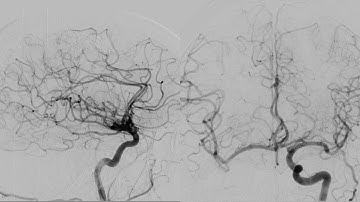

Stroke - Right M1 occlusion- Puncture to closure (1x)